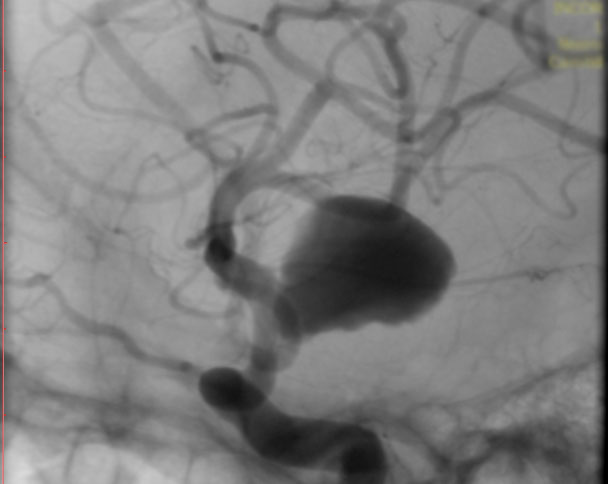

La paciente ingreso al Servicio de Hemodinamia el día martes 11 de febrero con un aneurisma cerebral gigante en la carótida izquierda y se le practicó una embolización; es decir una oclusión por dentro del mismo, donde se colocó un dispositivo denominado coils más un stent diversor de flujo. El procedimiento fue exitoso y contó con la colaboración de médicos neurointervencionistas del Instituto Oulton de la Ciudad de Córdoba.